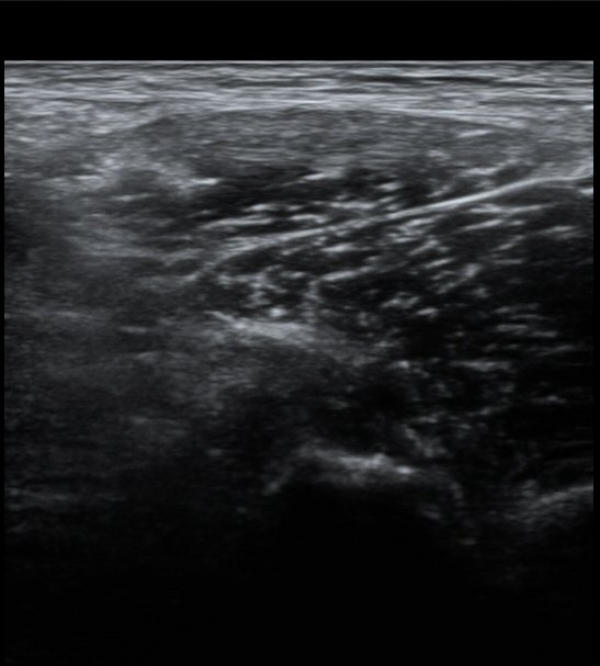

Àü»óÀå°ñ±Ø(ASIS) ¿¡¼­ 2~3cm ¾Æ·¡, 1~2cm ³»Ãø  ÀüÇÏÀå°ñ±Ø(AIIS) Á¾´Ü¸é°Ë»ç¿¡¼­

´ëÅðÁ÷±Ù ÈûÁÙÀÌ °í¿¡ÄÚ·Î Á¤»óÀûÀ¸·Î °üÂûµÇ³ª »À ºÎÂøºÎ¿¡ Àú¿¡ÄÚ º¯È­¸¦ º¸ÀδÙ(»çÁø 1).